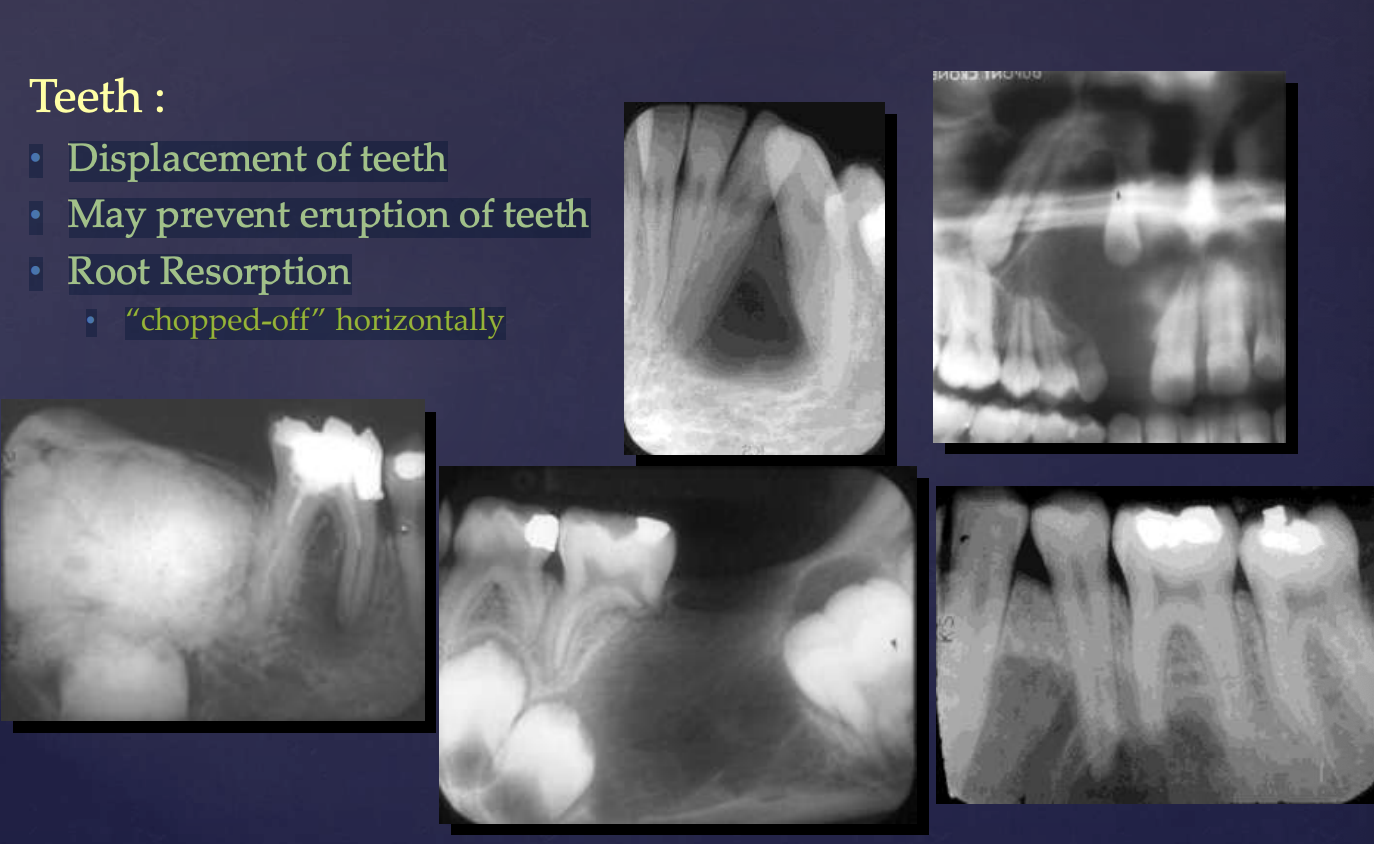

how do benign tumors effect surrounding structures: teeth?

• Displacement of teeth

• May prevent eruption of teeth

• Root Resorption → “chopped-off” horizontally